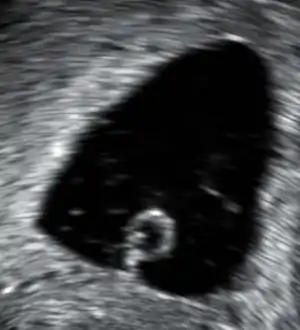

| سونوگرافی واژینال نشاندهندهٔ ساک جنینی به قطر ۲۸ میلیمتر است که هفت هفته و پنج روز از عمر آن میگذرد و تنها یک کیسه ناف از قسمت پایین بیرون زدهاست. بعد از اسکن کامل جنین در ساک پیدا نشده و تشخیص پزشک بارداری پوچ است. | |